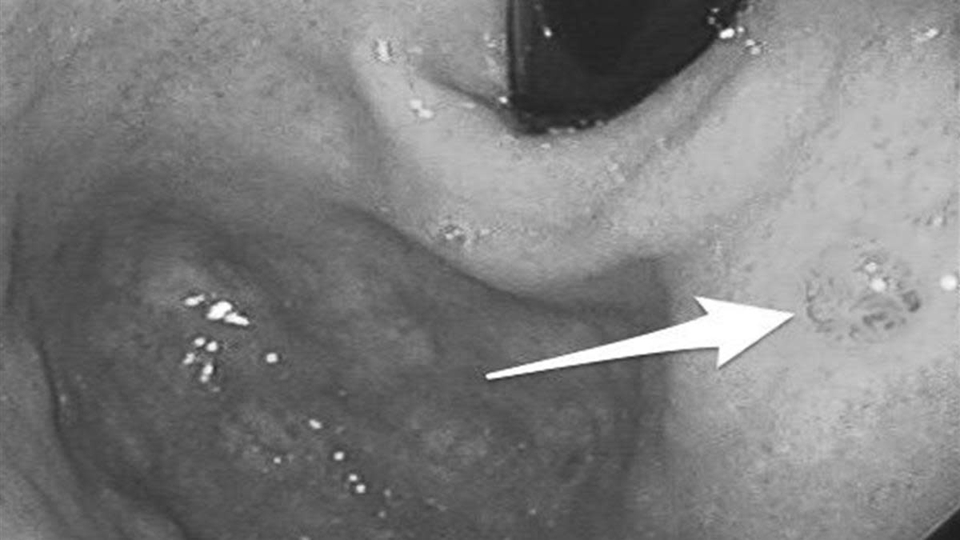

Cơ chế này chịu tác động của nhiều yếu tố. Nhiễm vi khuẩn Helicobacter pylori (HP), ăn mặn kéo dài hoặc thói quen sinh hoạt thất thường đều có thể làm suy yếu lớp bảo vệ niêm mạc dạ dày. Khi quá trình tổn thương và sửa chữa lặp lại nhiều lần nhưng không hoàn chỉnh, niêm mạc có thể xuất hiện “chuyển sản ruột” - một dạng tổn thương tiền ung thư.

Các tổng quan trên tạp chí The Lancet Oncology cho thấy nếu can thiệp từ giai đoạn tiền ung thư, tiên lượng có thể cải thiện hơn 50%. Tuy nhiên, điểm khó là giai đoạn này hầu như không gây đau dữ dội, mà chỉ là những thay đổi nhẹ, dễ bị xem nhẹ.